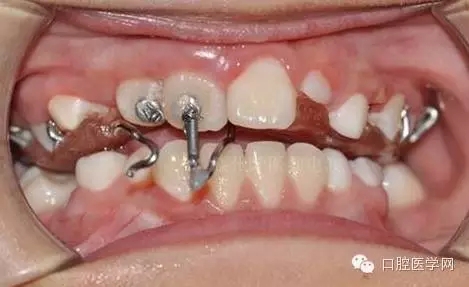

每周復(fù)診:清洗,加力,適當(dāng)調(diào)整吊桿方向

39.webp.jpg

40.webp.jpg

41.webp.jpg

42.webp.jpg

用時(shí)9周完成埋伏牙牽引。